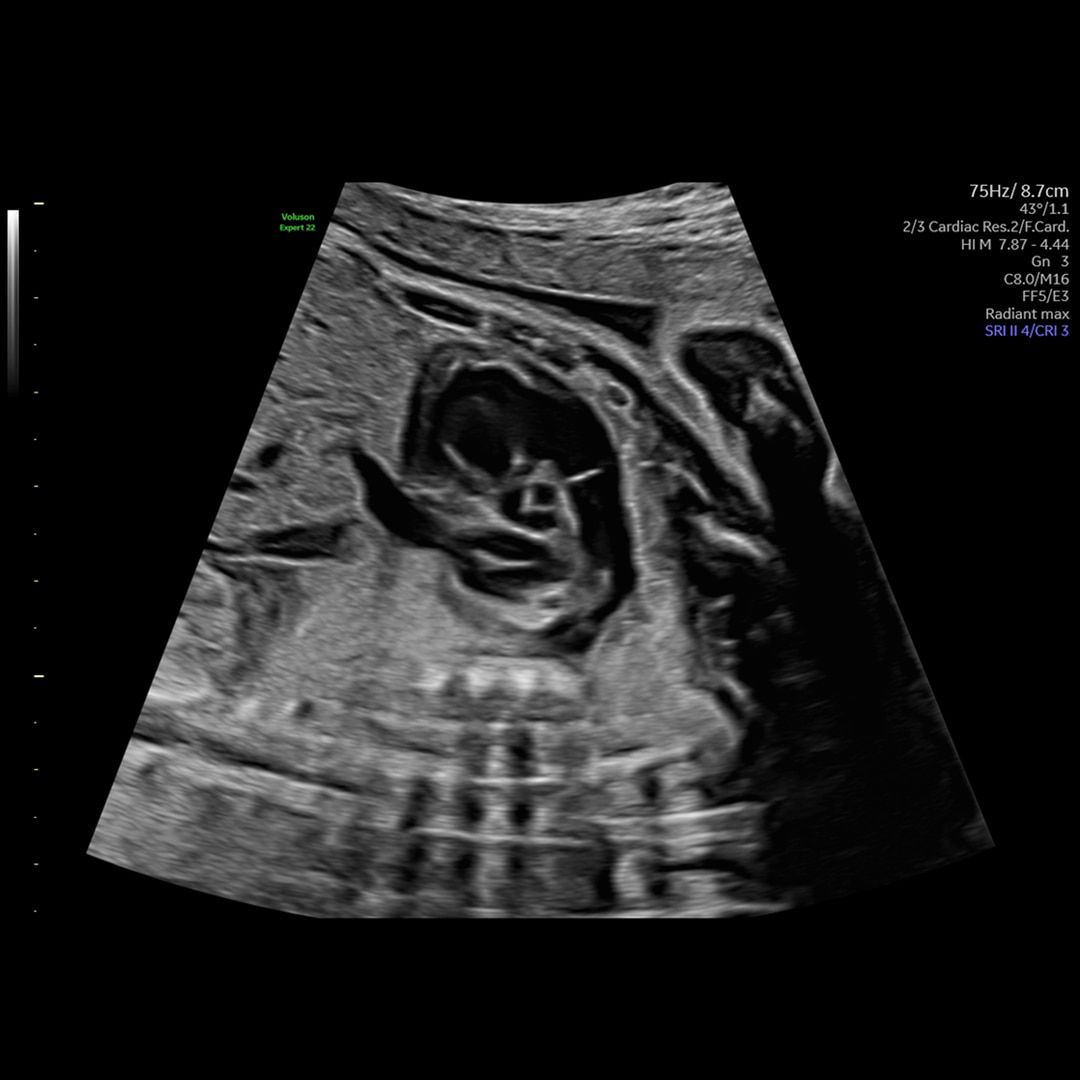

Radiant

Reach New Heights in 2D

Change the levels of elevation and enhance border visibility with Radiant. The result is a more 3D-like appearance, which aids in crucial border differentiation in anatomy such as brain and fetal heart